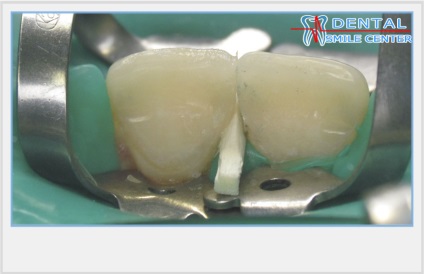

Modellezés fűrésszel vágott érintkező felületek.

Az eredeti eljárás ugyanazt a gyors, de biztonságos helyreállítás találkozott minket a mester osztályt a művészet helyreállítása az elülső fogak a bemutató Jeff Blank egy szimpóziumon évente megrendezett „Dentspy” az amerikai fogorvosok. Először szilikon minta helyreállítása az összes felső elülső fogak modellezett alapvetően palatális felülete és egy vágóéllel sarkok. Gumi gát hiányzik vagy mátrix vagy ékek, mint „gyilkos adhéziós” nem vonatkozik. Ezután az összes vágó részét egymást követően letétbe réteg dentin, zománc és világos színárnyalat modellezésével trowels vesztibuláris felületeket átmenetet az érintkező felületek. Végén a fogak már elválasztott egy fémes csiszoló szalag, amely a középső része a nem abrazív volt valami hasonlít egy fémfűrész. Modellezése érintkező felületek teljes befejező csíkok különböző súrlódástól.